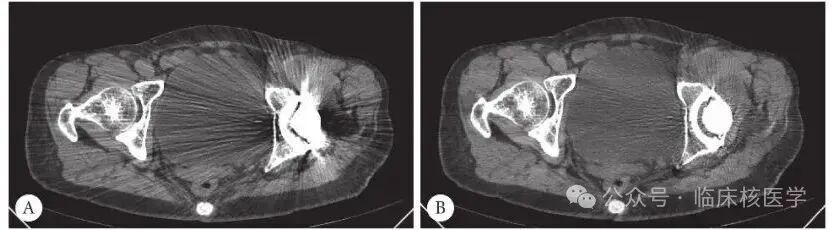

A:金属伪影例图(图片来源:北京右安门医院肿瘤中心)